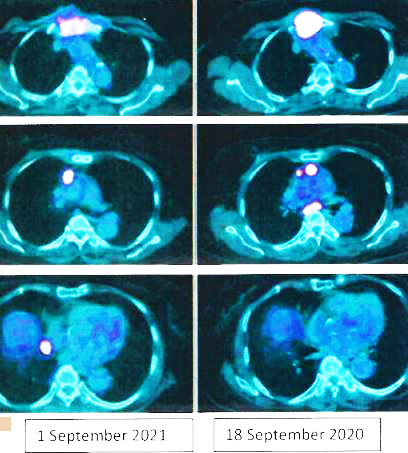

8. Pemindaian PET pada 14 April 2022 memang menunjukkan respon yang baik.

Sebelum kemo ———– setelah 6 siklus kemo

Kesimpulan:

1. Temuan scan menunjukkan respon metabolik lengkap pada kekambuhan dinding dada, metastasis nodal dan penyebaran jauh.

2. Perubahan atelektasis baru pada dasar paru kiri dengan efusi pleura kiri ringan mungkin disebabkan oleh infeksi baru-baru ini.

1. Hasil kemoterapi yang luar biasa.

Bandingkan ketiga gambar ini :

Kiri: Setelah operasi Lucy menjalani terapi alternatif, menolak kemoterapi. Hasilnya adalah metastasis luas (tengah).

Kanan: Lucy tidak punya pilihan selain menjalani kemoterapi. Hasil dari 6 siklus kemoterapi sungguh luar biasa! Selama lebih dari 25 tahun saya berurusan dengan pasien kanker, saya belum pernah melihat hasil kemoterapi yang luar biasa seperti ini. Salut dengan ahli onkologi! Anda menyelamatkan Lucy!

Faktanya, hasil chemo ini sangat sulit dipercaya sehingga orang tergoda untuk bertanya apakah itu asli dan bukan palsu? Jawaban saya TIDAK, studi detail hasil PET scan di bawah ini adalah nyata! Kaji gambar berikut dengan cermat – sebelum dan sesudah kemoterapi.